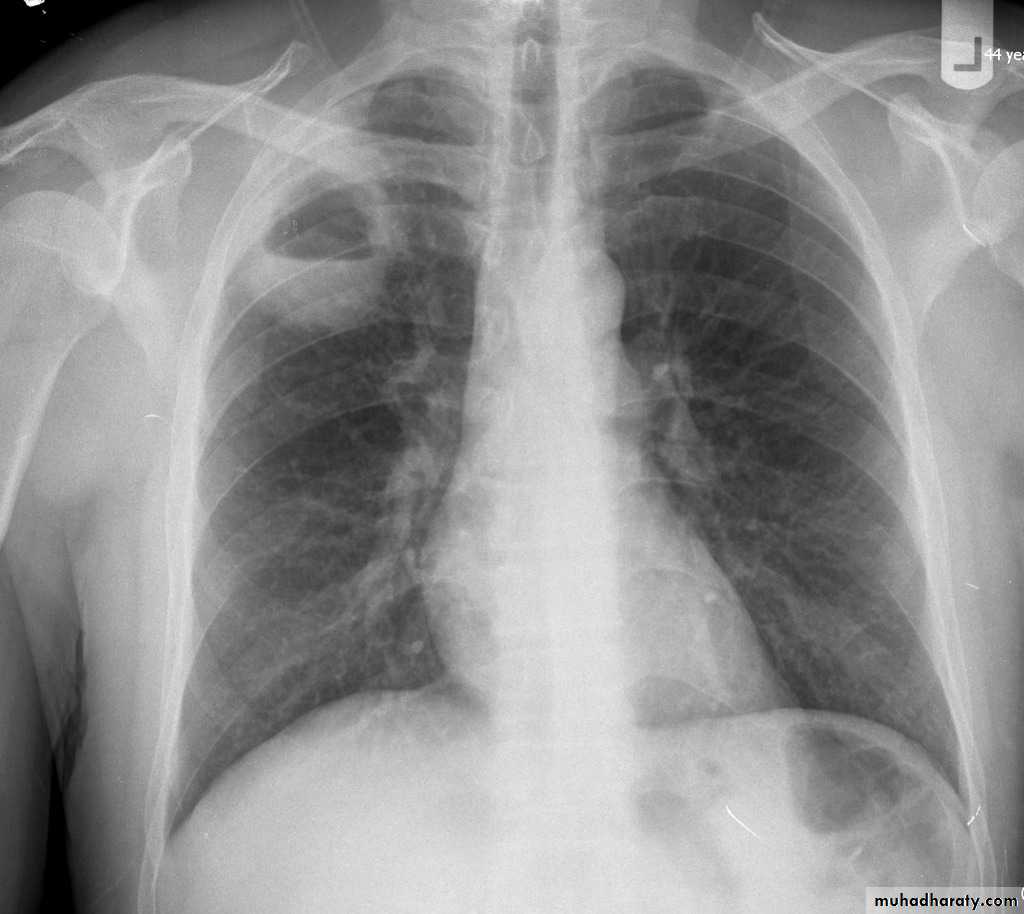

Lobular consolidation ( broncho or lobular pneumoniaCXR of adult ,PA and lateral views show:Patchy consolidation in both lung fields (diffuse) mainly in the lower zonesNormal heart size

Very important to consider that pulmonary edema in normal sized heart have close similar appearance to broncho pneumonia

The important Golden Key differentiation is the cardiac size being enlarged in pulmonary edema .